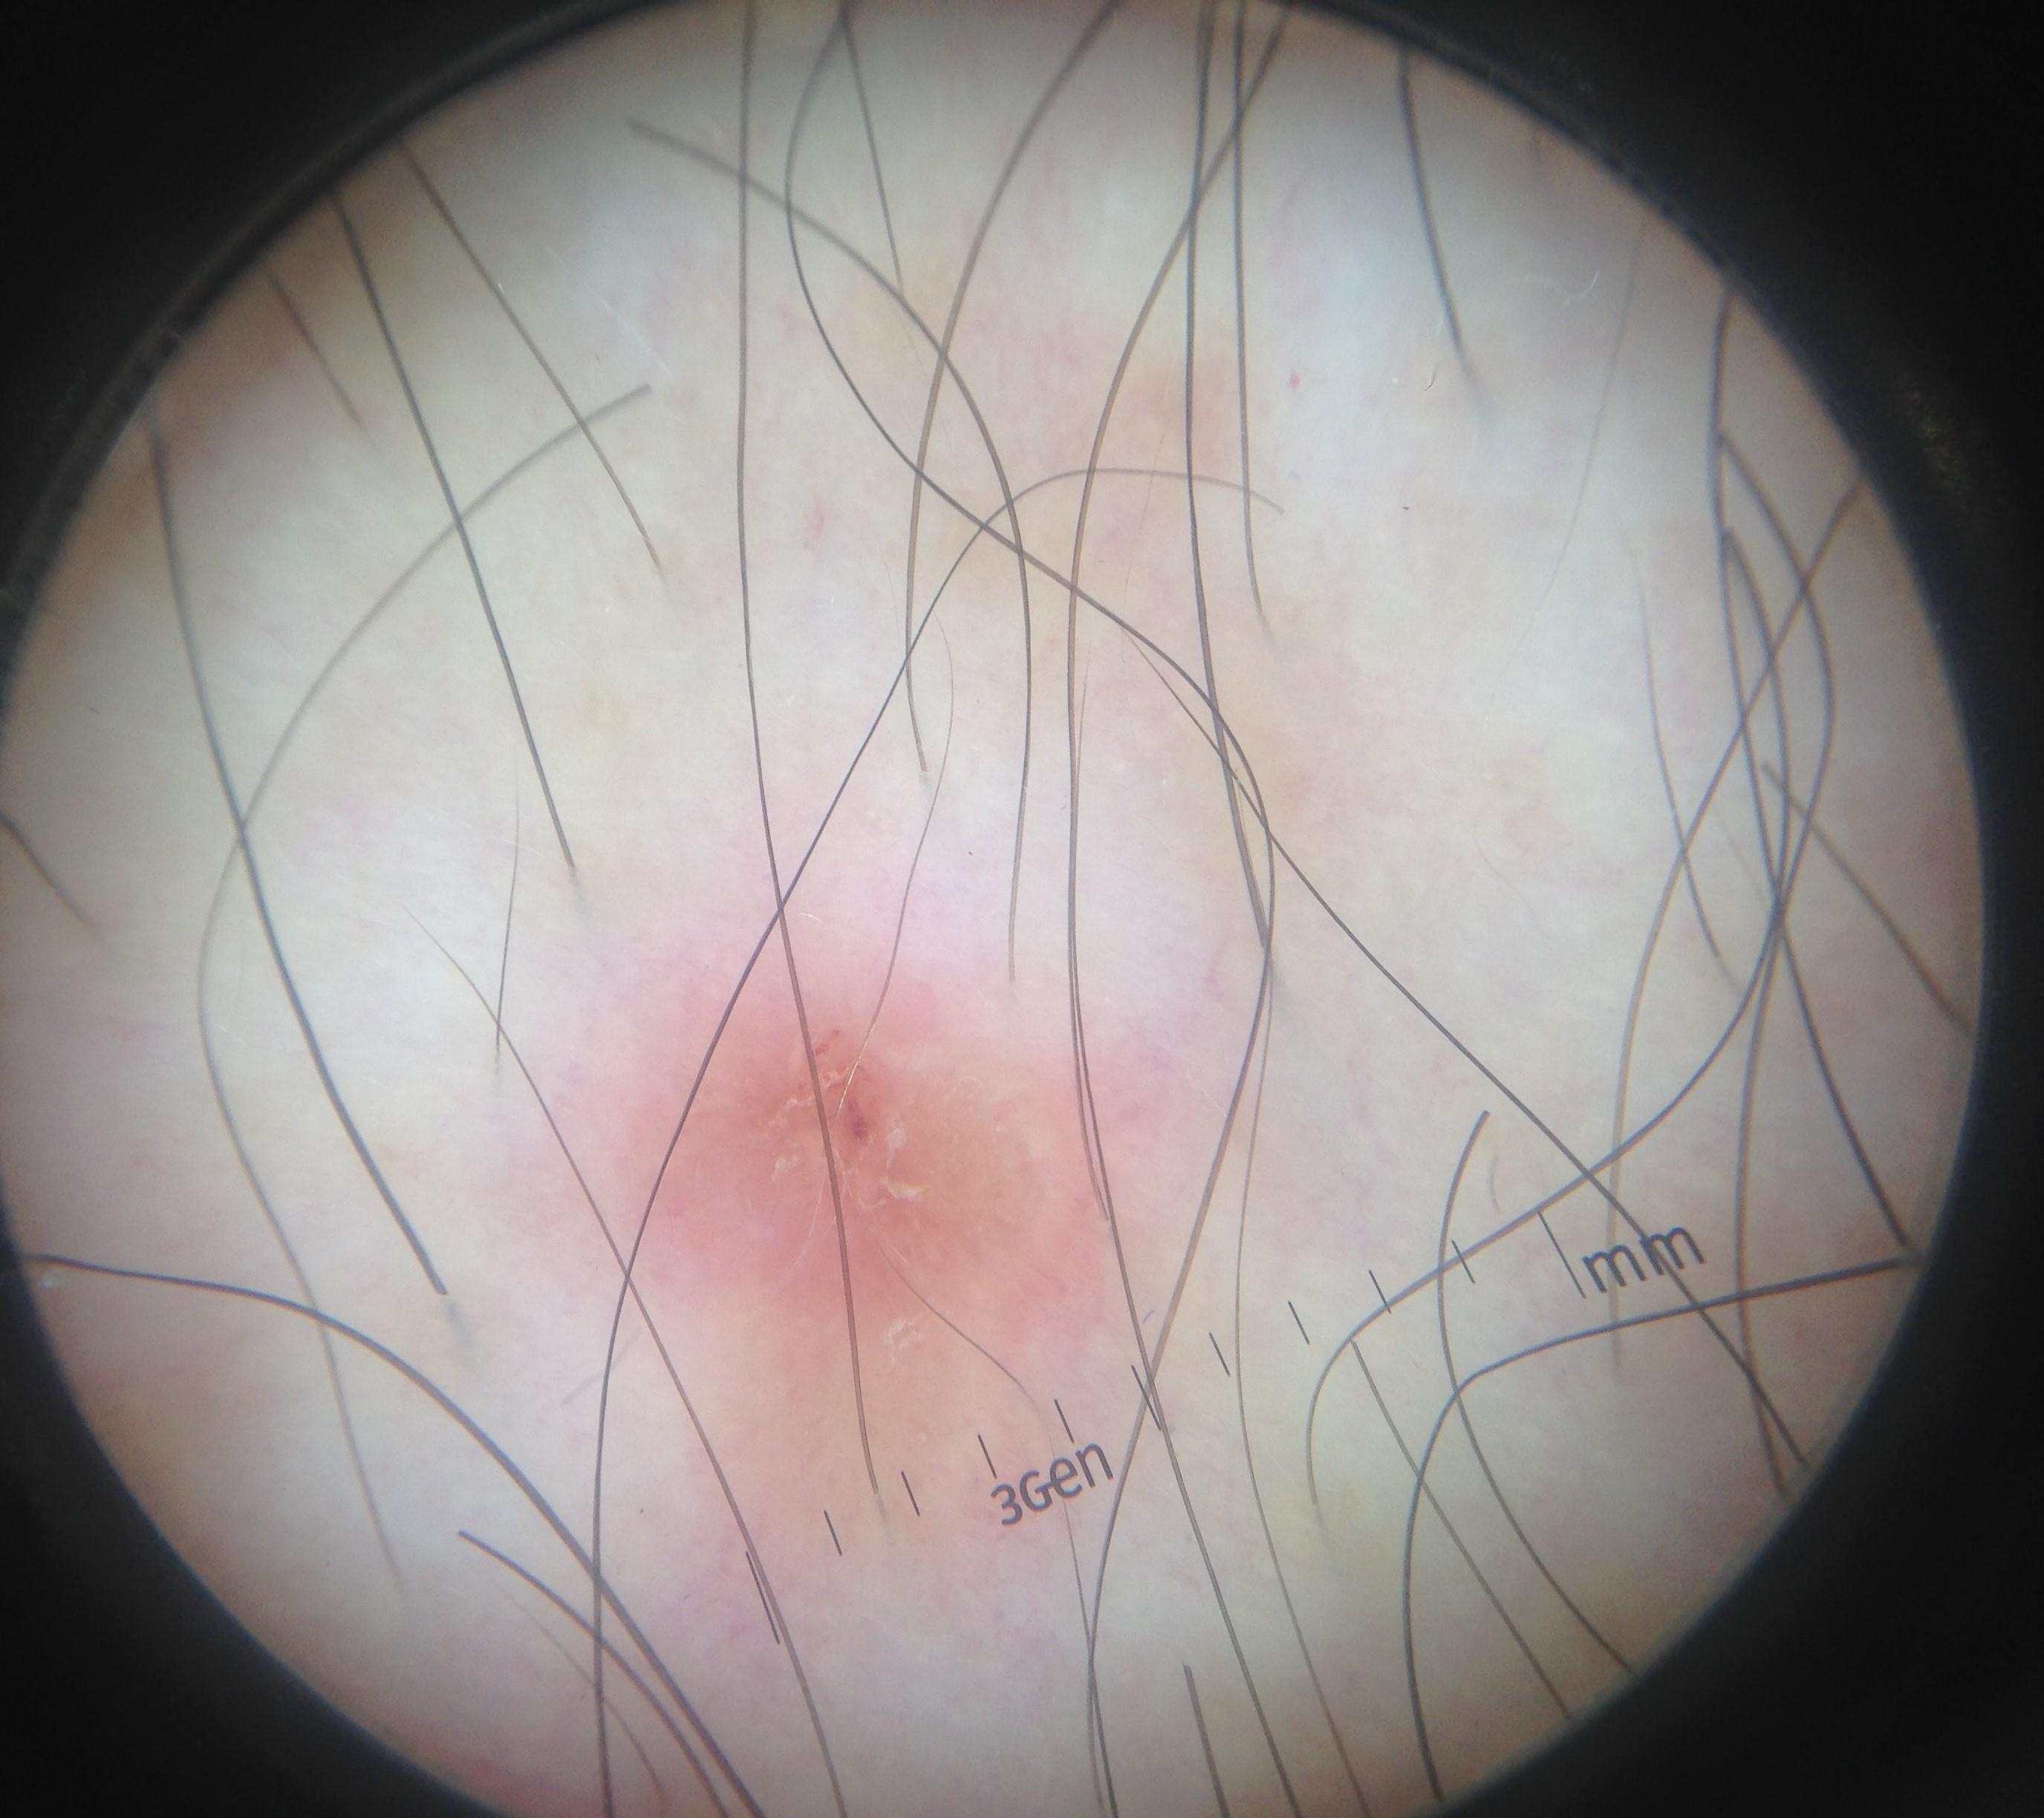

Skin lesion datasets provide essential information for understanding various skin conditions and developing effective diagnostic tools. They aid the artificial intelligence-based early detection of skin cancer, facilitate treatment planning, and contribute to medical education and research. Published large datasets have partially coverage the subclassifications of the skin lesions. This limitation highlights the need for more expansive and varied datasets to reduce false predictions and help improve the failure analysis for skin lesions. This study presents a diverse dataset comprising 12,345 dermatoscopic images with 40 subclasses of skin lesions, collected in Turkiye, which comprises different skin types in the transition zone between Europe and Asia. Each subgroup contains high-resolution images and expert annotations, providing a strong and reliable basis for future research. The detailed analysis of each subgroup provided in this study facilitates targeted research endeavors and enhances the depth of understanding regarding the skin lesions. This dataset distinguishes itself through a diverse structure with its 5 super classes, 15 main classes, 40 subclasses and 12,345 high-resolution dermatoscopic images.

Yilmaz, A., Yasar, S.P., Gencoglan, G. et al. DERM12345: A Large, Multisource Dermatoscopic Skin Lesion Dataset with 40 Subclasses. Sci Data 11, 1302 (2024). https://doi.org/10.1038/s41597-024-04104-3